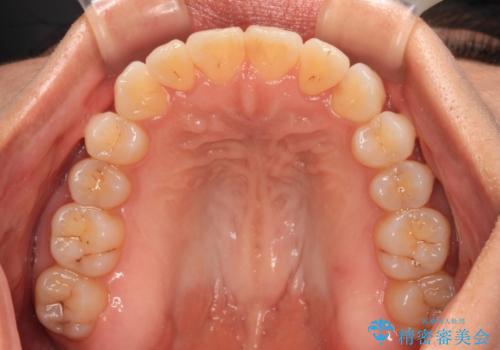

前歯のクロスバイト インビザラインによる矯正治療

- 上下のクロスバイトと前歯のデコボコを気にして来院された患者様です。

インビザラインを用い、IPR(歯と歯の間を削る)と歯列全体を拡大させることで、歯並びを整えていくこととしました。